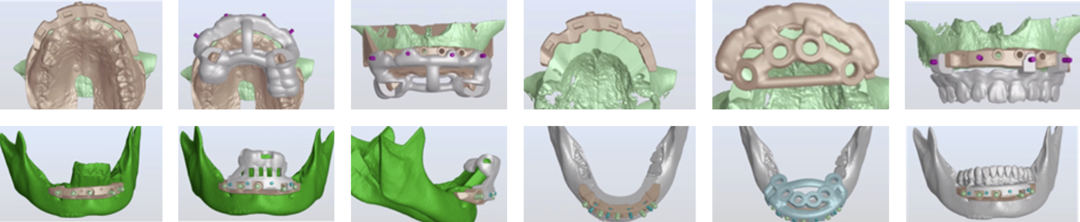

· 上下颌士卓曼360数字化导板 +预成临时修复体设计图。

· 士卓曼360导板包括:骨支持的基部导板 、牙支持的辅助导板 、就位于基部导板的种植导板 以及就位于基部导板的预成临时修复体组成。

· 上下颌计划行即刻种植,各植入六颗straumann钛锆种植体并行即刻修复。